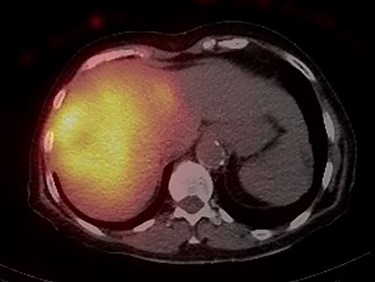

In 2018, the patient had a low dose chest CT for lung cancer screening, given her prior smoking history. The chest CT demonstrated a mass along the right hepatic dome. Triple-phase contrast-enhanced (ce) CT of the abdomen subsequently revealed a large multi-lobulated low-attenuation mass in the right hepatic lobe, predominantly involving Segments V and VIII and, to a lesser extent, Segments VI and VII, measuring 8.8 × 8.3 × 8.2 cm, and associated with a satellite lesion in Segment IVA, measuring 2.2 cm (Fig. 1). A PET CT was ordered and was negative for extrahepatic neoplastic disease.

Abdominal ceCT demonstrated an arterially enhancing mass with early washout characteristic of HCC; venous phase axial and coronal images are featured.